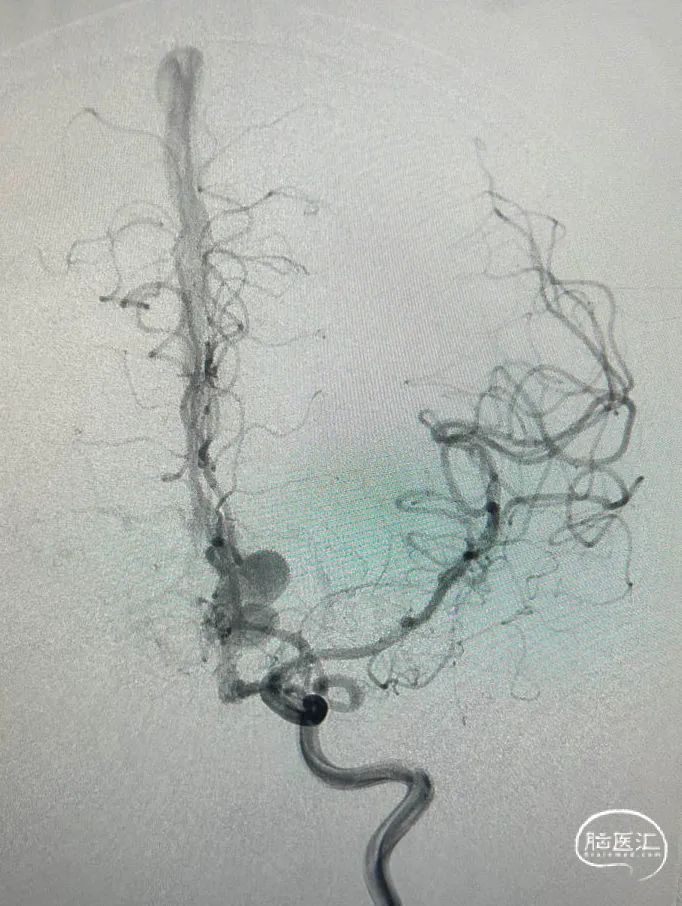

治疗经过

手术过程

第一根微导管到位。

第二根微导管到位及填圈所形成的塞子。

R-ica。

R-颈外也参与供血。

L-ica。

L-颈外也参与供血。

看来动脉路有戏,但保证胶一定不要返流到视网膜中央动脉。比较了一下,左侧眼动脉比较粗,从左侧眼动脉走,动脉高压锅努力搞起💪。一方面,可以让胶勇往直前,另一方面,可以防止胶逆流。

两侧的眼动脉用不同的方法进入。左边直接用Echelon超选,用另外一根微导管做塞子,塞子做在视网膜中央动脉开口的远端。

病人穿刺双侧股动脉鞘,通过左侧颈内动脉——眼动脉途径栓塞,右侧颈内动脉造影检查瘘口栓塞后情况。我们可以看到瘘口被栓得越来越少。

左边栓塞后,右侧颈内动脉3d旋转,仍然发现有瘘口残留,乘胜追击,一不做,二不休,既然病人决定要介入治疗,我们应该"连根铲除",避免复发。

左侧眼动脉栓塞术后。

右侧,想想左侧拔管的情况比较后怕,故换用Apollo,只能用HyperForm球囊,远端阻断提供支撑力,让Apollo进到瘘口。

微导管到位后的微导管造影情况,位置满意,斩草除根。

右侧眼动脉路径栓塞术后。

最后的onyx18胶-3d铸形,达到了治愈性栓塞的目的,病人也免得开颅之折腾。